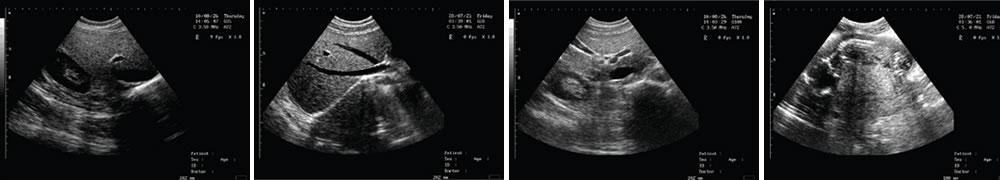

● 顯示模式:B、B/B、B+M、M、4B;

LED高清晰顯示器 一流的數(shù)字成像技術(shù)